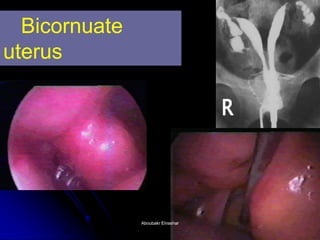

The document discusses the history and development of hysteroscopy. It began in 1869 but did not achieve routine use until improvements to optics, distension media, lighting and instruments in the 1970s-1990s allowed for office procedures without anesthesia. Today, many hysteroscopic procedures have replaced older, more invasive techniques. The document then provides details on rigid and flexible hysteroscopes, lighting sources, distension media, and diagnostic and operative uses of hysteroscopy for conditions like abnormal bleeding, infertility, uterine anomalies and assisted conception. Contraindications are also outlined.